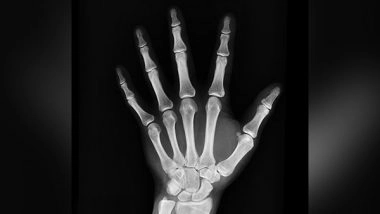

Washington [US], November 6 (ANI): Adult cancer survivors, particularly those diagnosed within five years and/or have a history of chemotherapy, have an increased risk for bone fractures, specifically pelvic and vertebral fractures, compared to older adults without cancer (ACS), according to a recent large study by researchers at the American Cancer Society.

The vertebral and pelvic fracture sites were mostly responsible for the greater fracture risk in cancer survivors. Chemotherapy recipients had a higher risk of fracture compared to cancer survivors who did not get chemotherapy; this link was more pronounced within five years of diagnosis but remained suggestive five years later.